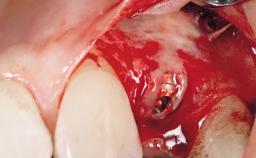

Immediate Placement of an Implant in a Maxillary Right Central Incisor Site

A 30-year-old female patient was referred to the office for the treatment of tooth 11. Her chief concern at the initial visit was to inquire, “Why is my tooth pink?” Upon clinical examination, it was determined that tooth 11 had a previous history of trauma and that the clinical crown had become noticeably pink in color as a result of internal resorption. This diagnosis was confirmed radiographically, indicating a large radiolucency involving the central and distal portions of the clinical crown. It was determined that restoration of this tooth was not possible, and that extraction was indicated. The presence of a mid-line diastema, which the patient wanted to reproduce, directed the treatment plan for tooth replacement utilizing a dental implant.

| Bone Augmentation | Horizontal|Simultaneous |

| Augmentation Materials | Autogenous chips|Membrane |

| Placement Protocol | Immediate implant placement |

| Socket Integrity | Sufficient, with intact bone walls |

| Bone Volume | Sufficient, with intact walls |